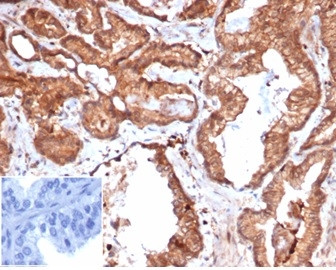

Product information "Anti-CD47 / IAP (Integrin Associated Protein), recombinant antibody, clone rCD47/6365"

Formulation: Purified Ab WITHOUT BSA and Azide at 1.0mg/ml. Cellular Localization: Cell membrane. Positive Control: brain or ovarian tumors (IHC)., HUVEC or OVCA3 cells (IF/FACS). Human placenta, Jurkat, MCF-7. Chromosome Location: 3q13.12. Protein Function: Adhesive protein that mediates cell-to-cell interactions (PubMed:11509594, PubMed:15383453). Acts as a receptor for thrombospondin THBS1 and as modulator of integrin signaling through the activation of heterotrimeric G proteins (PubMed:19004835, PubMed:7691831, PubMed:8550562). Involved in signal transduction, cardiovascular homeostasis, inflammation, apoptosis, angiogenesis, cellular self-renewal, and immunoregulation (PubMed:11509594, PubMed:15383453, PubMed:19004835, PubMed:27742621, PubMed:32679764, PubMed:7691831, PubMed:8550562). Plays a role in modulating pulmonary endothelin EDN1 signaling (PubMed:27742621). Modulates nitrous oxide (NO) signaling, in response to THBS1, hence playing a role as a pressor agent, supporting blood pressure (By similarity). Plays an important role in memory formation and synaptic plasticity in the hippocampus (By similarity). Receptor for SIRPA, binding to which prevents maturation of immature dendritic cells and inhibits cytokine production by mature dendritic cells (PubMed:11509594). Interaction with SIRPG mediates cell-cell adhesion, enhances superantigen-dependent T-cell-mediated proliferation and costimulates T-cell activation (PubMed:15383453). Positively modulates FAS-dependent apoptosis in T-cells, perhaps by enhancing FAS clustering (By similarity). Plays a role in suppressing angiogenesis and may be involved in metabolic dysregulation during normal aging (PubMed:32679764). In response to THBS1, negatively modulates wound healing (By similarity). Inhibits stem cell self-renewal, in response to THBS1, probably by regulation of the stem cell transcription factors POU5F1/OCT4, SOX2, MYC/c-Myc and KLF4 (By similarity). May play a role in membrane transport and/or integrin dependent signal transduction (PubMed:7691831). May prevent premature elimination of red blood cells (By similarity) [The Uniprot Consortium]

| Application: | IHC |